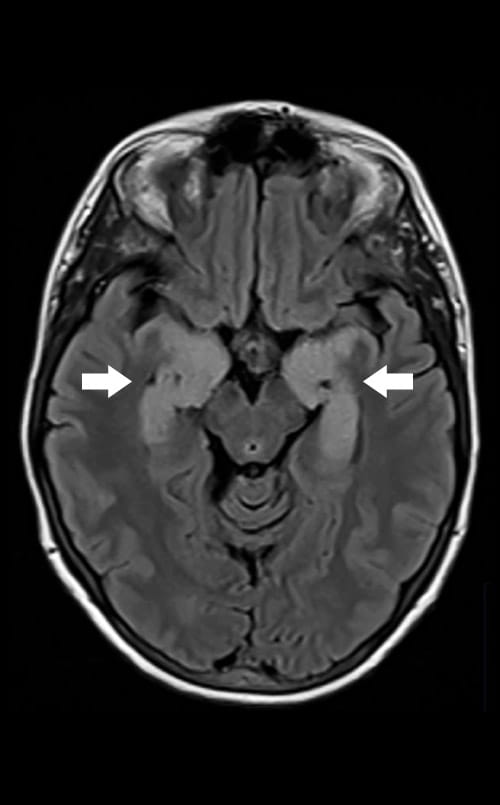

Arrows on an MRI image point to inflammation of the limbic system in a patient with autoimmune encephalitis.